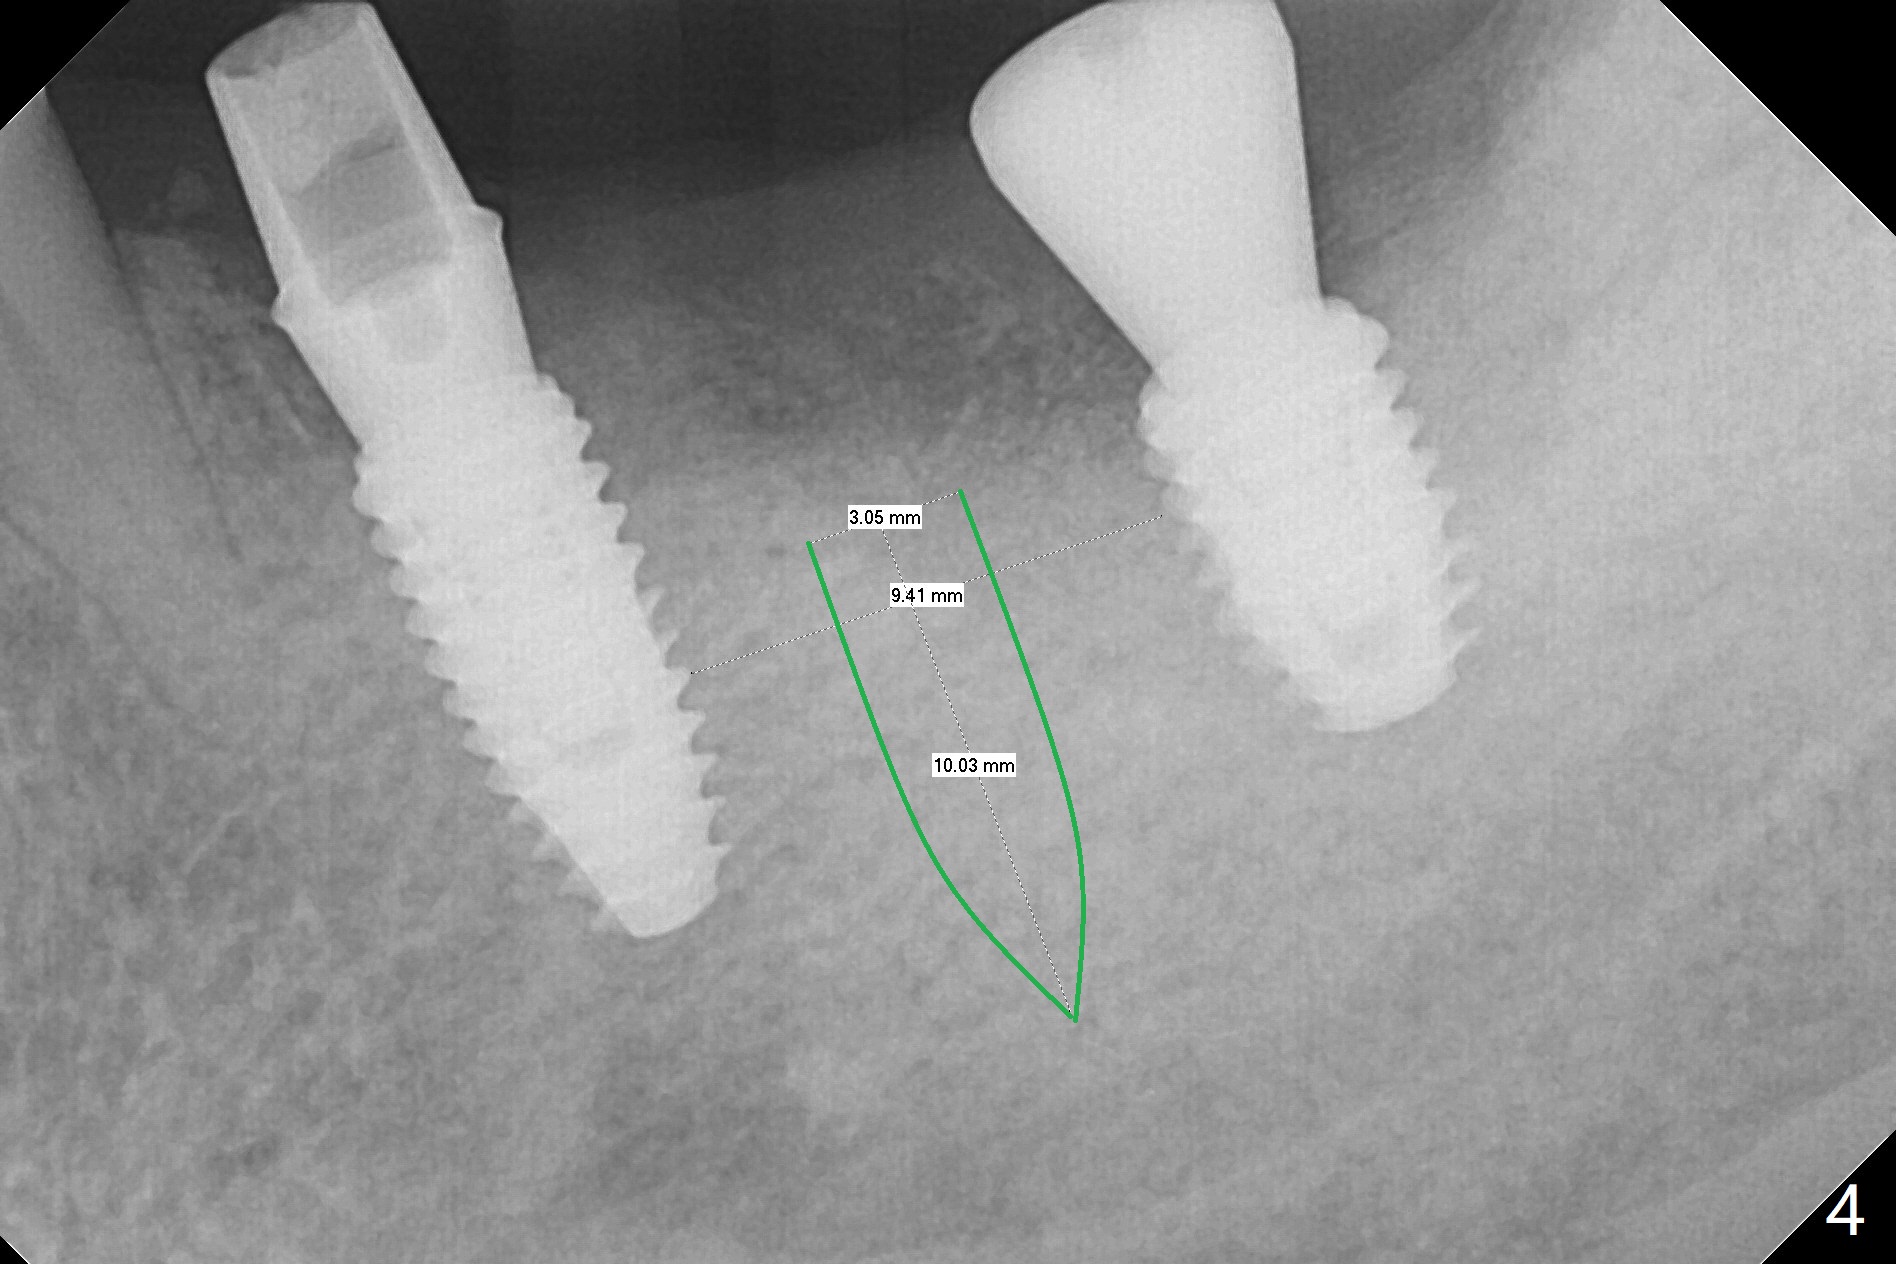

PA is taken after a 2.2 mm drill reaches the depth at #12, since osteotomy is initiated in the mesial slope of the socket (Fig.1 red dashed line) and the neighboring root (*) slightly curves distal. A 8.6x5 mm healing abutment is used to close the socket with the large mesiodistal space after bone graft (Fig.2 *). In contrast, the socket at #20 is large; a 4.5x4.5(3) mm cementation abutment is placed for an immediate provisional to keep autogenous bone (harvested from the site of #18) in place (Fig.3). Six months postop, the patient does not want implant FPD. She wants an additional implant at #19. Since the space between the implants #18 and 20 is 9.41 mm, a narrow implant is indicated (3 or 3.5 mm, Fig.4), in spite of the sufficient buccolingual width (Fig.5). The position and trajectory of the 1.2 mm initial drill and 3x10(2) mm 1-piece implant are acceptable with free hand (Fig.6,7). After 3-4 more turns, panoramic X-ray (Fig.8) and CT (Fig.9) are taken for 28-30 guide. It appears that the 1-piece implant is placed acceptable buccolingual (Fig.9 B). The implants at #12,18,20 (4.5 months postop with guide) are shown in Fig.10-12. It appears that guided surgery is superior in buccolingual position and trajectory to free hand. There is crestal remodeling without implant thread exposure 11 months postop (Fig.13).